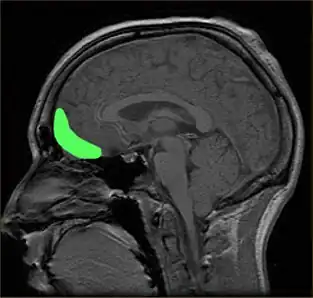

Dysfunctions in the prefrontal cortex and amygdala regions of the brain have been associated with specific learning impairments in psychopathy. Since the 1980s, scientists have linked traumatic brain injury, including damage to these regions, with violent and psychopathic behavior. Patients with damage in such areas resembled "psychopathic individuals" whose brains were incapable of acquiring social and moral knowledge; those who acquired damage as children may have trouble conceptualizing social or moral reasoning, while those with adult-acquired damage may be aware of proper social and moral conduct but be unable to behave appropriately. Dysfunctions in the amygdala and ventromedial prefrontal cortex may also impair stimulus-reinforced learning in psychopaths, whether punishment-based or reward-based. People scoring 25 or higher in the PCL-R, with an associated history of violent behavior, appear to have significantly reduced mean microstructural integrity in their uncinate fasciculus—white matter connecting the amygdala and orbitofrontal cortex. There is evidence from DT-MRI of breakdowns in the white matter connections between these two important areas.[126][127][128]

Brain injury

Researchers have linked head injuries with psychopathy and violence. Since the 1980s, scientists have associated traumatic brain injury, such as damage to the prefrontal cortex, including the orbitofrontal cortex, with psychopathic behavior and a deficient ability to make morally and socially acceptable decisions, a condition that has been termed "acquired sociopathy", or "pseudopsychopathy".[135] Individuals with damage to the area of the prefrontal cortex known as the ventromedial prefrontal cortex show remarkable similarities to diagnosed psychopathic individuals, displaying reduced autonomic response to emotional stimuli, deficits in aversive conditioning, similar preferences in moral and economic decision making, and diminished empathy and social emotions like guilt or shame.[149] These emotional and moral impairments may be especially severe when the brain injury occurs at a young age. Children with early damage in the prefrontal cortex may never fully develop social or moral reasoning and become "psychopathic individuals ... characterized by high levels of aggression and antisocial behavior performed without guilt or empathy for their victims". Additionally, damage to the amygdala may impair the ability of the prefrontal cortex to interpret feedback from the limbic system, which could result in uninhibited signals that manifest in violent and aggressive behavior.[126][137]

A 2008 review by Weber et al. suggested that psychopathy is sometimes associated with brain abnormalities in prefrontal-temporo-limbic regions that are involved in emotional and learning processes, among others.[159] Neuroimaging studies have found structural and functional differences between those scoring high and low on the PCL-R in a 2011 review by Skeem et al. stating that they are "most notably in the amygdala, hippocampus and parahippocampal gyri, anterior and posterior cingulate cortex, striatum, insula, and frontal and temporal cortex".[7][160]

The amygdala and frontal areas have been suggested as particularly important.[127] People scoring 25 or higher in the PCL-R, with an associated history of violent behavior, appear on average to have significantly reduced microstructural integrity between the white matter connecting the amygdala and orbitofrontal cortex (such as the uncinate fasciculus). The evidence suggested that the degree of abnormality was significantly related to the degree of psychopathy and may explain the offending behaviors.[128] Furthermore, changes in the amygdala have been associated with "callous-unemotional" traits in children. However, the amygdala has also been associated with positive emotions, and there have been inconsistent results in the studies in particular areas, which may be due to methodological issues.[7]

Some of these findings are consistent with other research and theories. For example, in a neuroimaging study of how individuals with psychopathy respond to emotional words, widespread differences in activation patterns have been shown across the temporal lobe when psychopathic criminals were compared to "normal" volunteers, which is consistent with views in clinical psychology. Additionally, the notion of psychopathy being characterized by low fear is consistent with findings of abnormalities in the amygdala, since deficits in aversive conditioning and instrumental learning are thought to result from amygdala dysfunction, potentially compounded by orbitofrontal cortex dysfunction, although the specific reasons are unknown.[137][161]

Considerable research has documented the presence of the two subtypes of primary and secondary psychopathy.[162][163] Proponents of the primary-secondary psychopathy distinction and triarchic model argue that there are neurological differences between these subgroups of psychopathy which support their views.[164] For instance, the boldness factor in the triarchic model is argued to be associated with reduced activity in the amygdala during fearful or aversive stimuli and reduced startle response, while the disinhibition factor is argued to be associated with impairment of frontal lobe tasks. There is evidence that boldness and disinhibition are genetically distinguishable.[7]